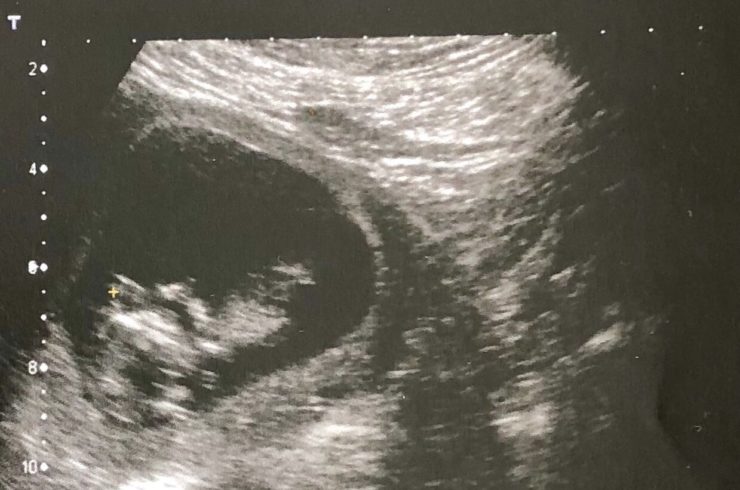

We had our first scan here in Portugal, pic below, which was a gas experience as our Portuguese was woeful and the sonographer didn’t speak any English. Luckily, we both had a bit of Spanish and managed to muddle our way through.

Our second scan was back in Dublin in Holles St and though the pictures from it are indecipherable smudges, the experience of seeing our baby's heart beating and legs kicking was surreal and wonderful. I’ve been feeling more kicks since then (and Ben has even felt a few too), which is both insanely cute and very sci-fi.

(On a more sombre, but important, side note, it was our first scan I was referring to in this tweet. The thought that I wouldn’t be able to go home for medical care and support if something had been detected at that early scan filled me with sadness and anger and is one of many, many reasons why it’s so crucial that we trust women and repeal the 8th next week ❤).